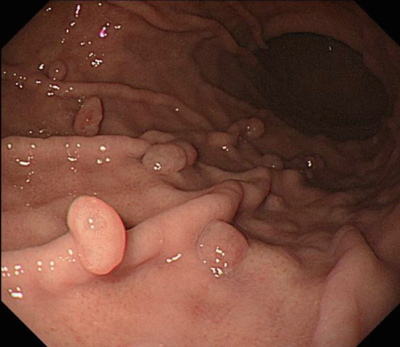

検査所見:尿所見:蛋白(-)、糖(-)、潜血(-)、沈渣に白血球を認めない。血液所見:赤血球400万、Hb 12.1g/dL、Ht 40%、白血球8,200、血小板30万。心電図と胸部エックス線写真とに異常を認めない。上部消化管内視鏡像を別に示す。

考えられる診断はどれか。

a. 胃GIST

b. 1型胃癌

c. 0-IIa型胃癌

d. 胃底腺ポリープ

e. 胃MALTリンパ腫